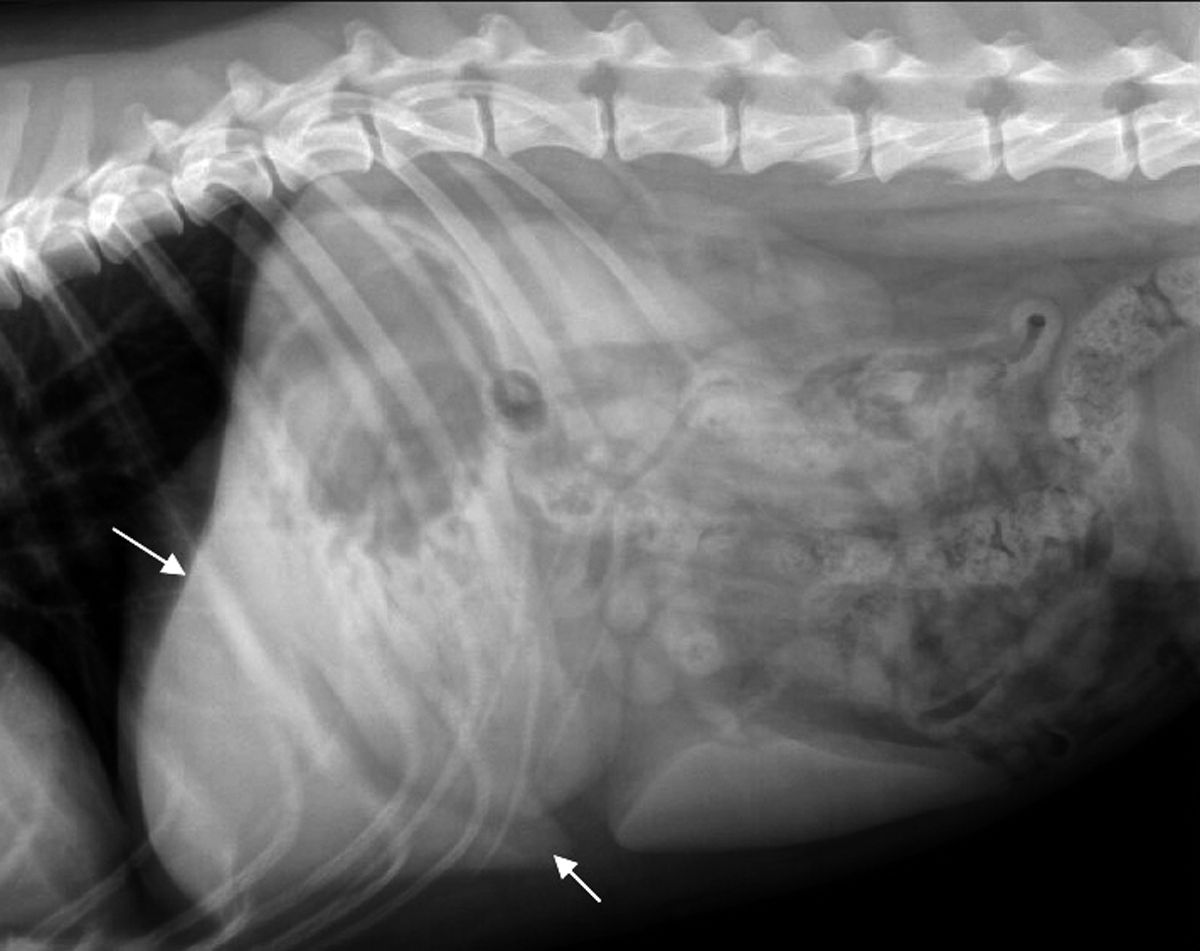

Figure 1 — A radiograph of a dog presented for abdominal distension Dog Abdomen X Ray the imaging anatomy web site is a basic atlas of normal imaging anatomy of domestic animals. The following radiographs are the left lateral and ventrodorsal views of the abdomen of a. The ventrodorsal (vd) view where the pet is laying on its back. canine abdomen example 1. There is also a dv view with a pet. the. Dog Abdomen X Ray.